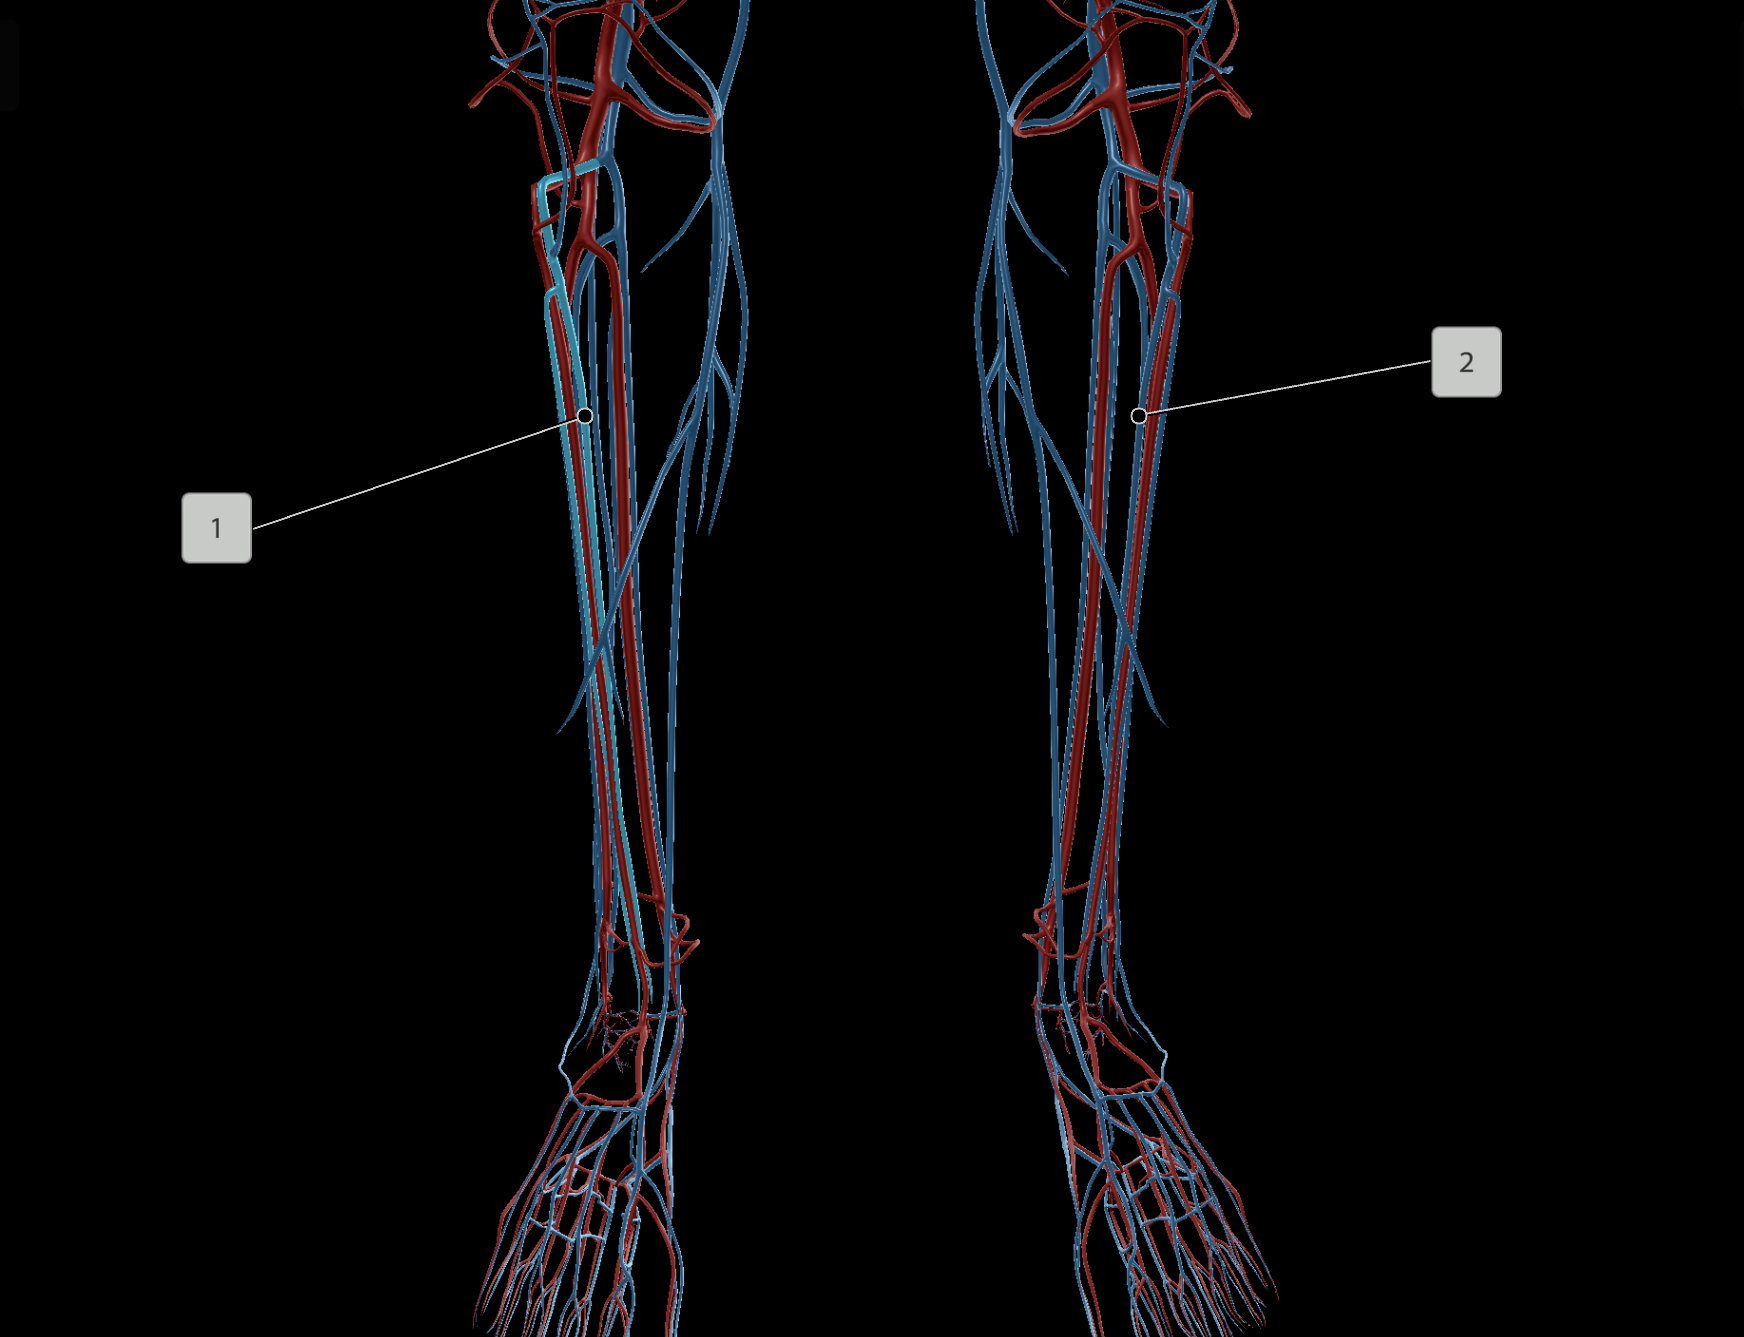

Anterior Tibial Artery

Posterior Tibial Artery

Anterior Tibial Vein

Posterior Tibial Vein

Great Saphenous Vein

Peroneal Artery